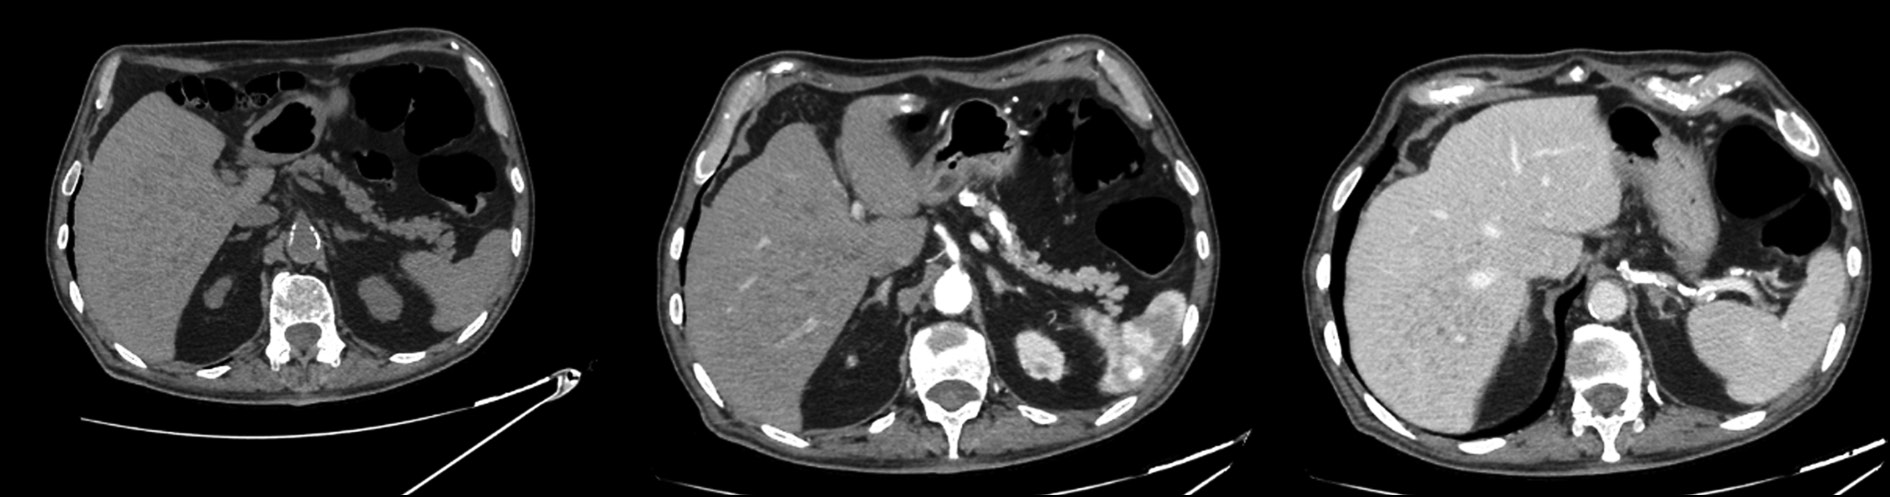

Идиопатическая инвагинация кишечника: результаты визуализации неотложной абдоминальной патологии

Инвагинация кишечника у взрослых — редкая причина кишечной непроходимости и обычно связана с неопластическими заболеваниями. Идиопатические формы встречаются крайне редко. В статье описывается случай инвагинации кишечника у молодой женщины, которая испытывала симптомы кишечной непроходимости. Представлены результаты визуализации.

Первичных заболеваний при гистологическом исследовании выявлено не было. Пациентка поступила в больницу для проведения компьютерной томографии из-за постоянных болей в животе. Компьютерная томография выявила инвагинацию кишечника с вовлечением илеоцекального клапана и купола слепой кишки, а также отёчность и утолщение стенок париетальной брюшины. Идиопатическая инвагинация кишечника — редкое неотложное состояние органов брюшной полости у взрослых. Симптомы могут быть персистирующими, стёртыми и неясными, что затрудняет постановку точного диагноза. В таких случаях решающее значение имеет диагностическая визуализация. Некоторые результаты компьютерной томографии, такие как мишеневидное содержимое кишечника, могут указывать на данное заболевание.